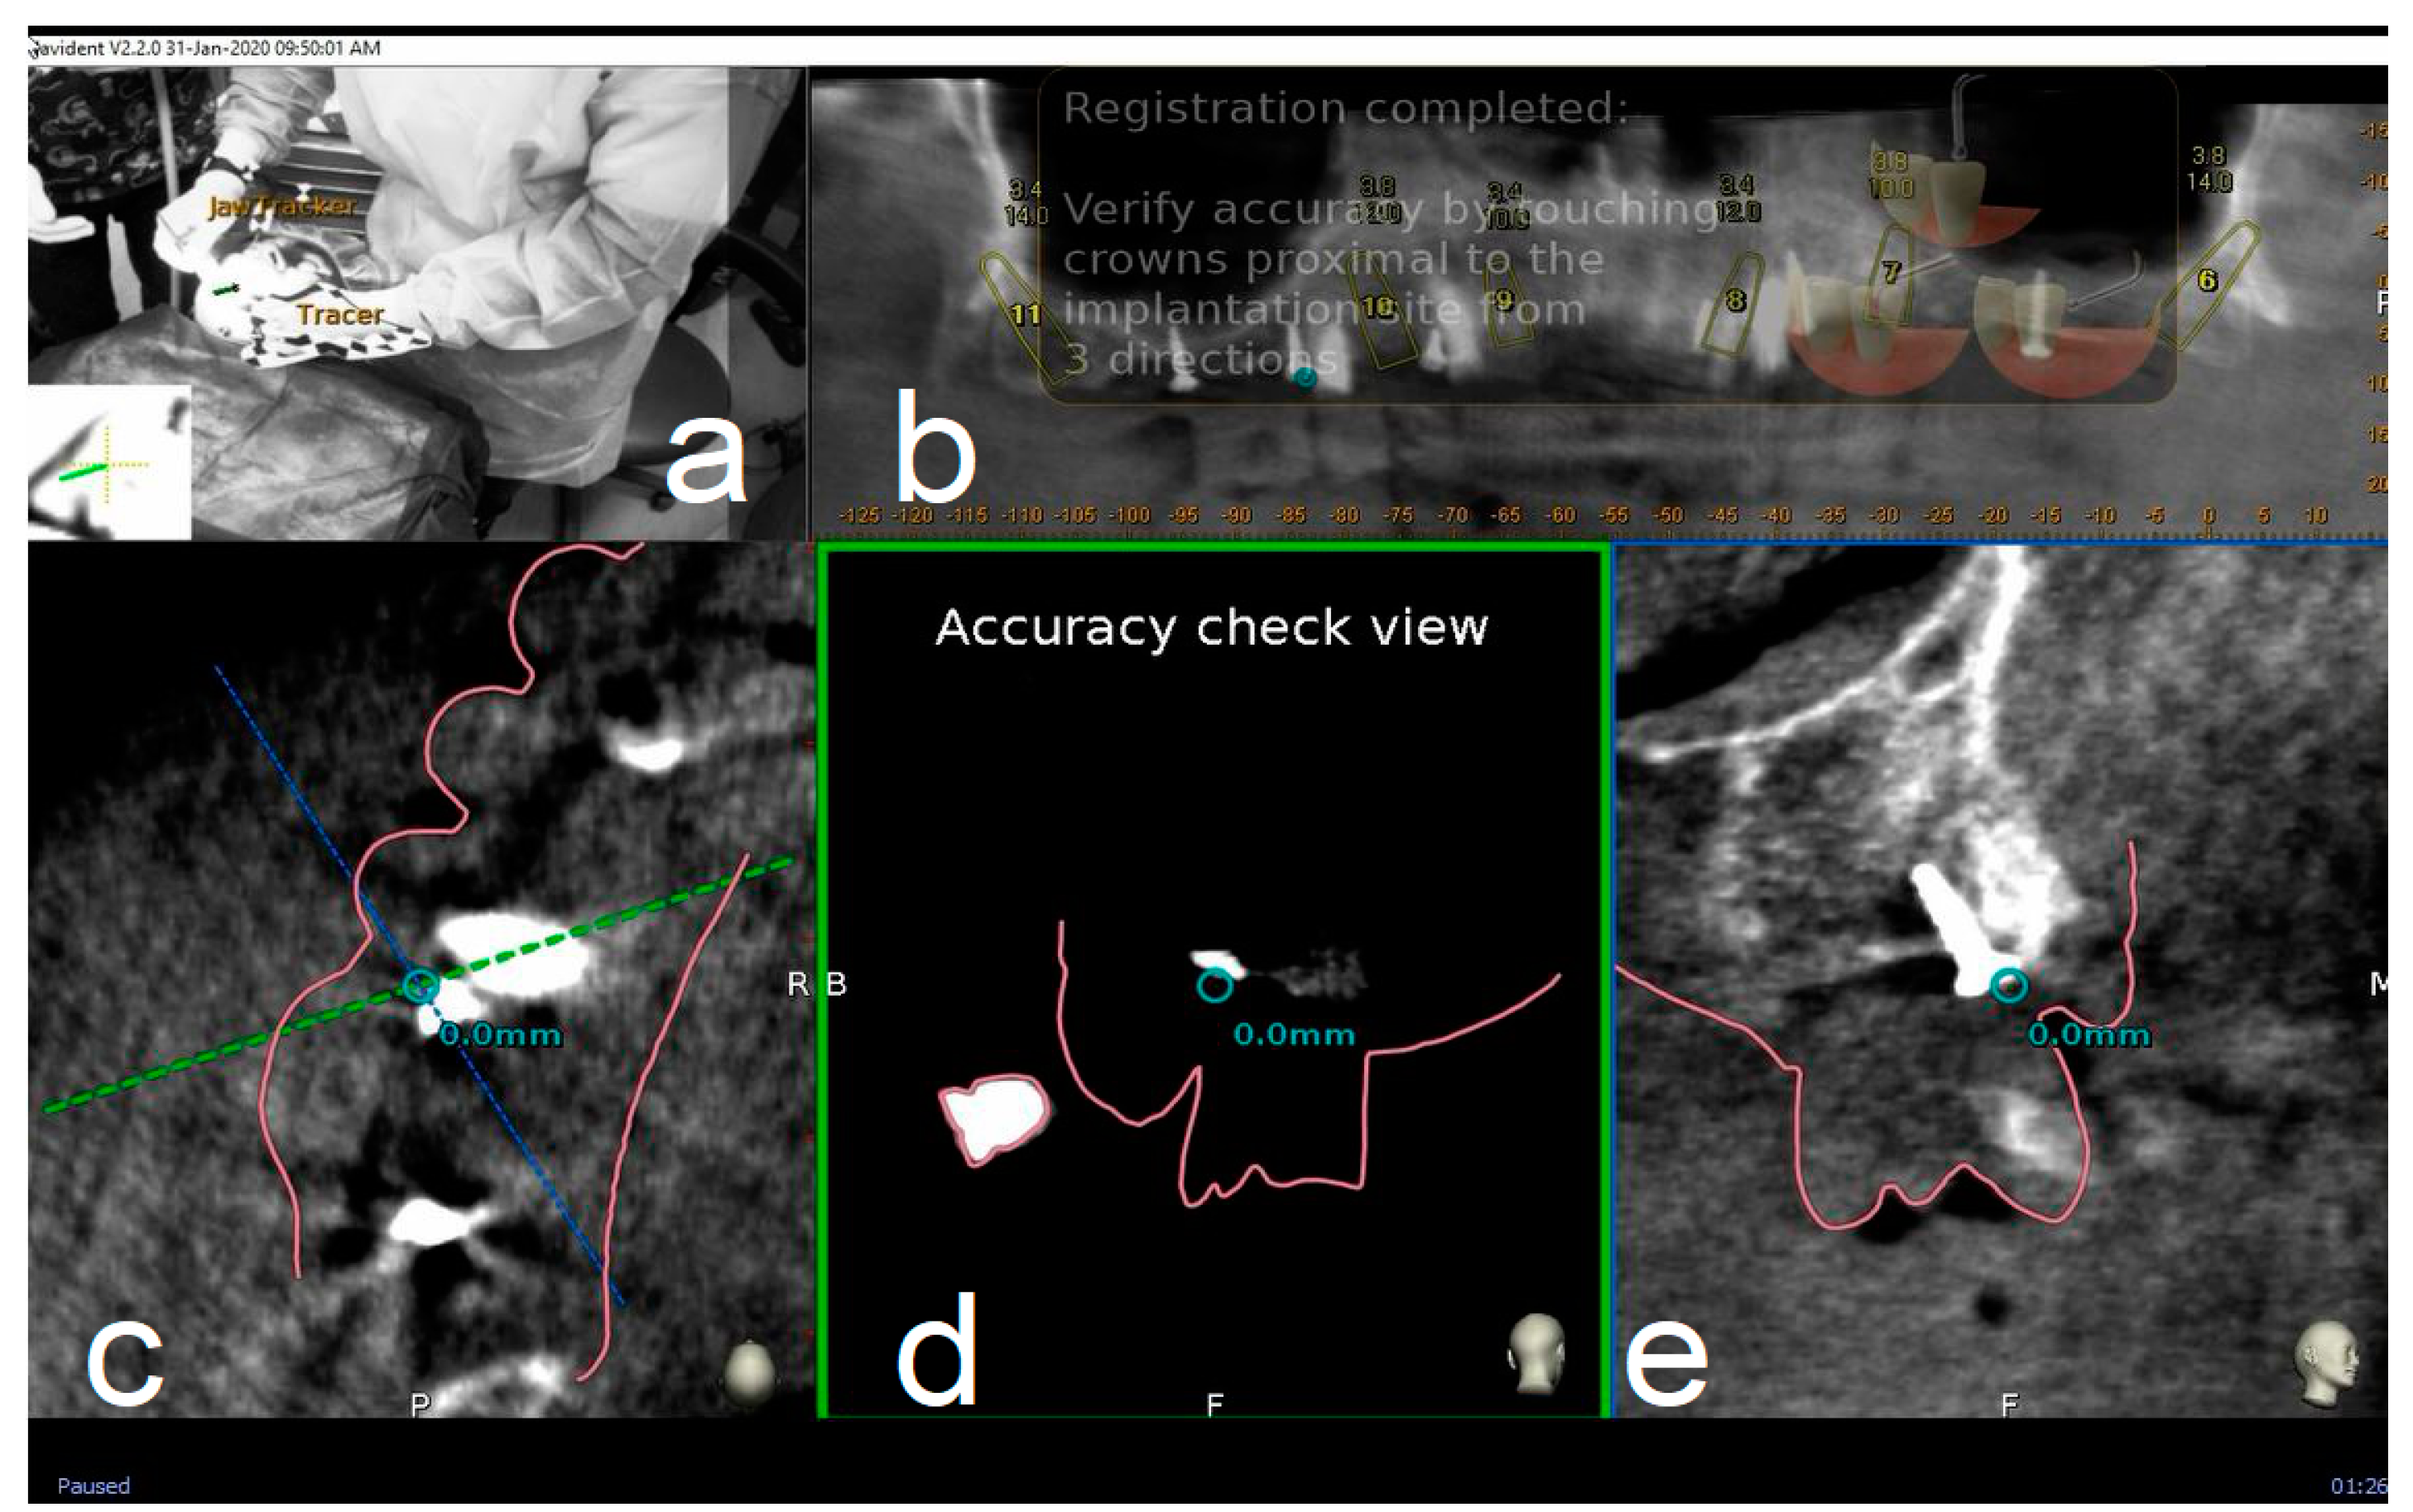

2.4.2. Trace

To track the patient’s jaw by the system cameras, an optical tracking tag needs to be fixed to the patient’s jaw where the surgery has to be performed. This requires a JawTracker™ to be connected to 1–2 teeth in the patient residual dentition by light-curing composite resin or by anchoring with mini screws into bone. Alternatively, but only in the maxilla, a HeadTracker™ can be used for tracking by placing it directly on the patient’s head (Figure 2). Tracing can then be performed starting at landmark locations. During tracing, the surgeon slides the tracer’s ball tip in full contact with each landmark surface (if Salvin™ mini screws are used, software automatically recognized them once they come into contact with the tracer) (Figure 3).

After all selected landmarks/teeth are traced, the software automatically performs registration. Sampled trace points get superimposed with CBCT 3D rendering. The complete trace and registration process takes an average of 1–2 min. The accuracy of trace registration is then assessed by touching with tracer’s ball tip any patient’s anatomical marker and confirming congruency between the touched marker and what is shown on the laptop screen (Figure 4). If the accuracy check is not satisfactory, the tracing process can be immediately repeated.

Figure 4.

The surgeon (a) can then verify the registration accuracy (b) by touching with the tracer’s ball tip one of the patient’s landmark (mini screw used in this case) (c). The matching quality can be verified from each view (d,e).